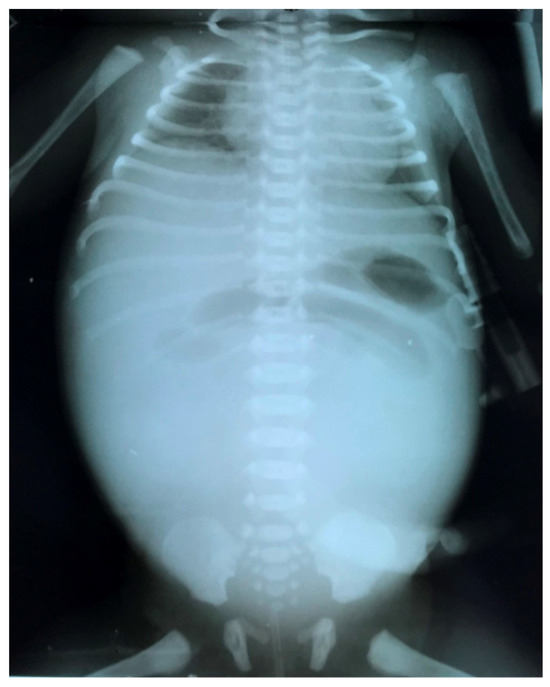

3.2.2. Complicated Meconium Ileus